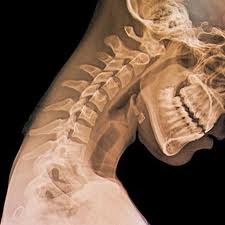

Osteoporosis is a decrease in the calcification or density of bone as well as reduced bone mass, and increase in the space between bones, resulting in porosity and fragility.

- Chronic vertebral fractures may result in significant lower-back pain.

Avoid excessive spinal loading on squat and leg press exercises.